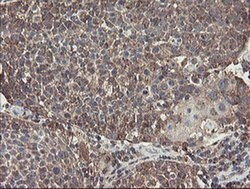

ACBD3 Monoclonal Antibody for Western Blot, IHC (P), Flow

| Flow Cytometry, Immunohistochemistry (Paraffin), Western Blot | |